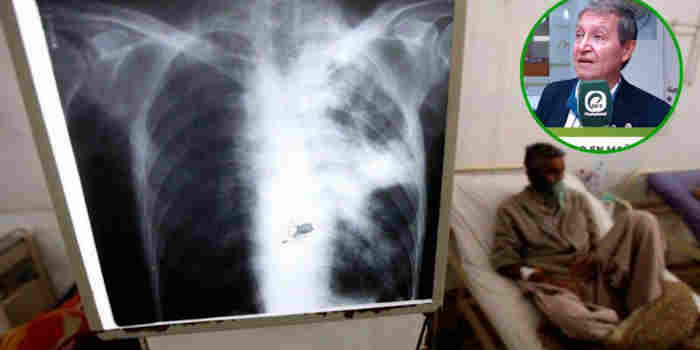

El doctor Bernardo Biella, en su columna semanal por Profesional FM, advirtió que, junto a Jujuy, las provincias del norte son las principales portadoras de la enfermedad.

Salta y Jujuy son las provincias que más pacientes con tuberculosis tienen, informó el doctor Bernardo Biella en su columna semana por Profesional FM.

Sostuvo que se tenían detectadas 400 casos hasta que se pidió una vigilancia sanitaria, por lo tanto, se salió a testear y buscar pacientes, con lo cual los diagnósticos se duplicaron. No porque hayan aumentado los casos sino porque siempre estuvieron ahí, pero se desconocían.

El médico dijo que se contagia por contacto estrecho prolongado, por al menos 8 horas, los principales síntomas son fiebre vespertina y pérdidas de apetito. Se detecta sobre todo en sectores humildes, de carencia económica, no obstante, la enfermedad no discrimina y la puede tener cualquiera.

Indicó que los medicamentos son muy costosos, pero afortunadamente los da el Estado, para tratamientos de seis meses.